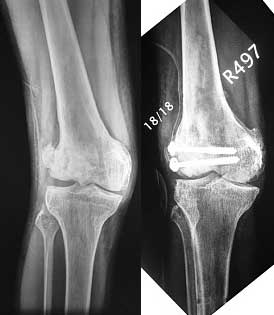

Re: Interesting case - what would you do? Knee val

послал Mangal Parihar 30 Апрель 2007, 17:18

I opened it up from the lateral aspect.

Freed up the non-union site with minimal disturbance to the posterior and lateral soft tissue attachments on the lateral condyle fragment.

Applied a distractor between femoral shaft and tibia, to create a space on the lateral aspect.

This brought the lateral condylar fragment into a position that seemed to be reasonably well aligned, but showed up a bone gap.

This was fixed temporarily, bone grafted with tricortical struts, and fixed by two cancellous screws. The fragment was not large enough to afford any fixation to a plate or such implant, and the screws held it compressed well to the rest of the distal femur.

Post-op - limb is well aligned, rom 0-30, but I am not pushing that right now, for the next two or three weeks.

Further plan - hope that the screws hold the fragment appropriately till union, but if the stability on table is anything to judge by, that should not be a problem.

Quadricepsplasty after a year or so, to restore flexion.

Pictures attached.

Mangal Parihar